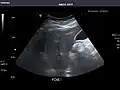

Right kidney -